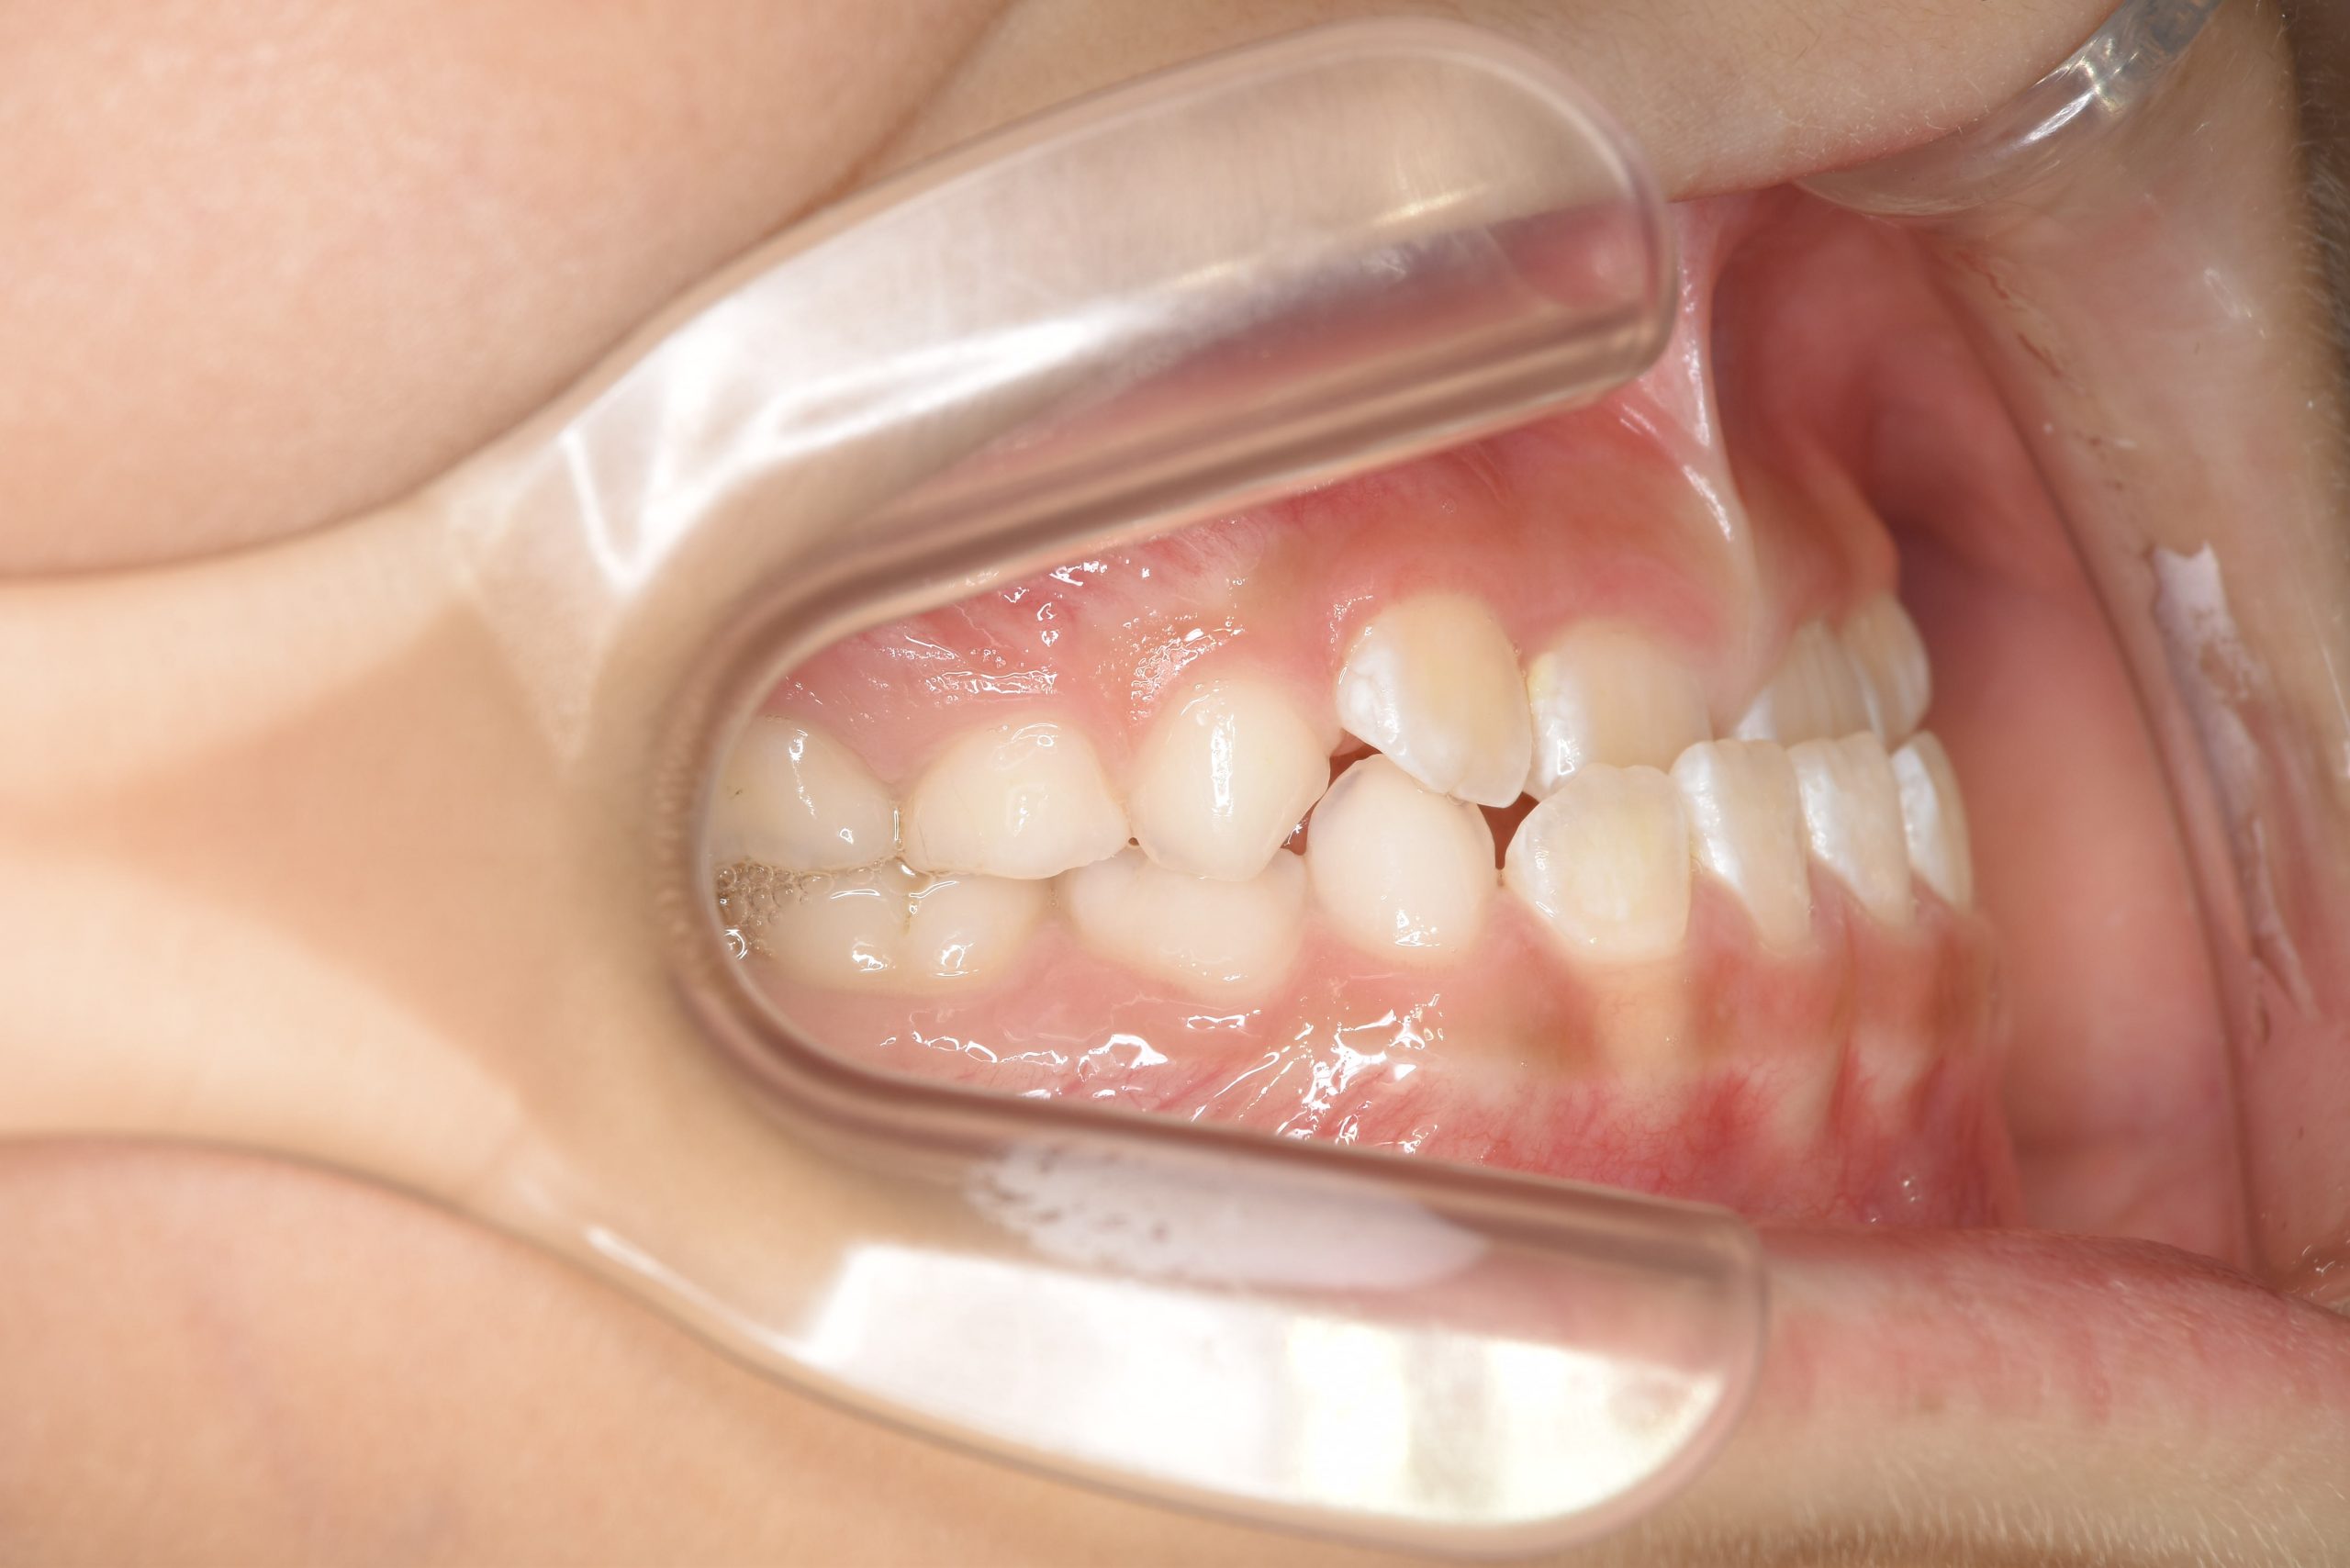

ビフォー

子どもの矯正治療|症例_858

主訴 下顎が出ている

施術内容 上顎急速拡大装置と下顎リンガルアーチを用いて上下顎骨を拡大した。

上顎前方牽引装置を用いて上顎骨を前方に成長促進させた。

その後マウスピース型矯正装置で歯牙を配列し良好な咬合を獲得した。